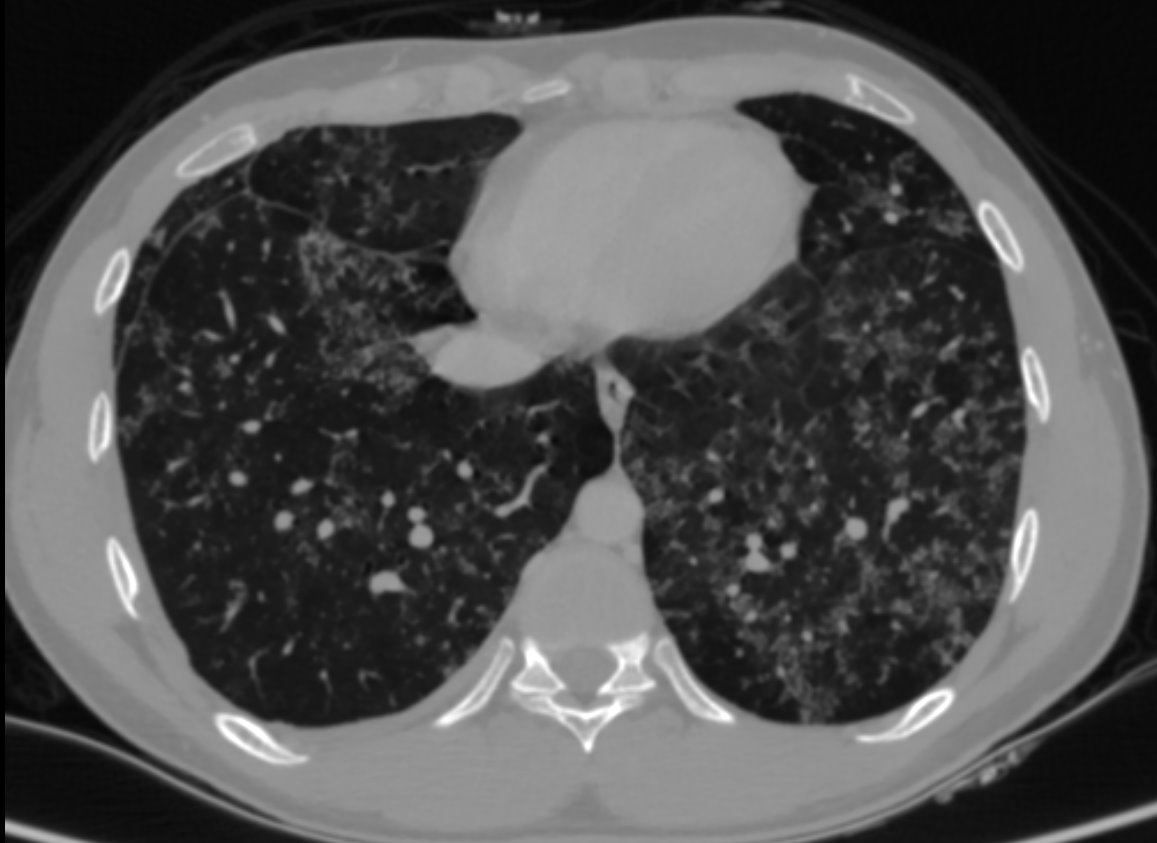

• HRCT thorax was performed.

• Numerous patchy nodular parenchymal infiltrates distributed diffusely in all the lung lobes, with a peribronchovascular and subpleural distribution.

• Apical emphysematous changes.

• No significant mediastinal lymphadenopathy seen. No effusion

• Alveolar sarcoidosis

• Patchy lung opacities 1–4 cm, rounded or elongated

• Irregular, blurred margins, may show air bronchograms

• Located along bronchovascular bundles or subpleural

• Galaxy sign: opacity with many surrounding small nodules (granulomas)

• Fairy ring / Reverse halo: circular arrangement of opacities with central clearing

• Nodules, ground-glass opacities,

• Thickened bronchovascular bundles,

• Thickened interlobular septa